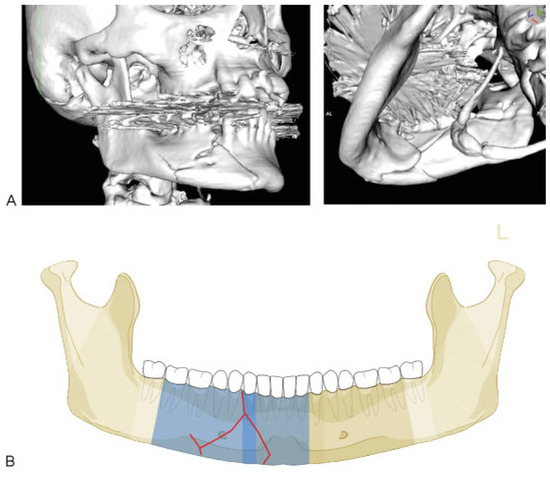

Condylar Process

Case Examples

Appendix A. Additional level 2 coding examples of mandibular fractures